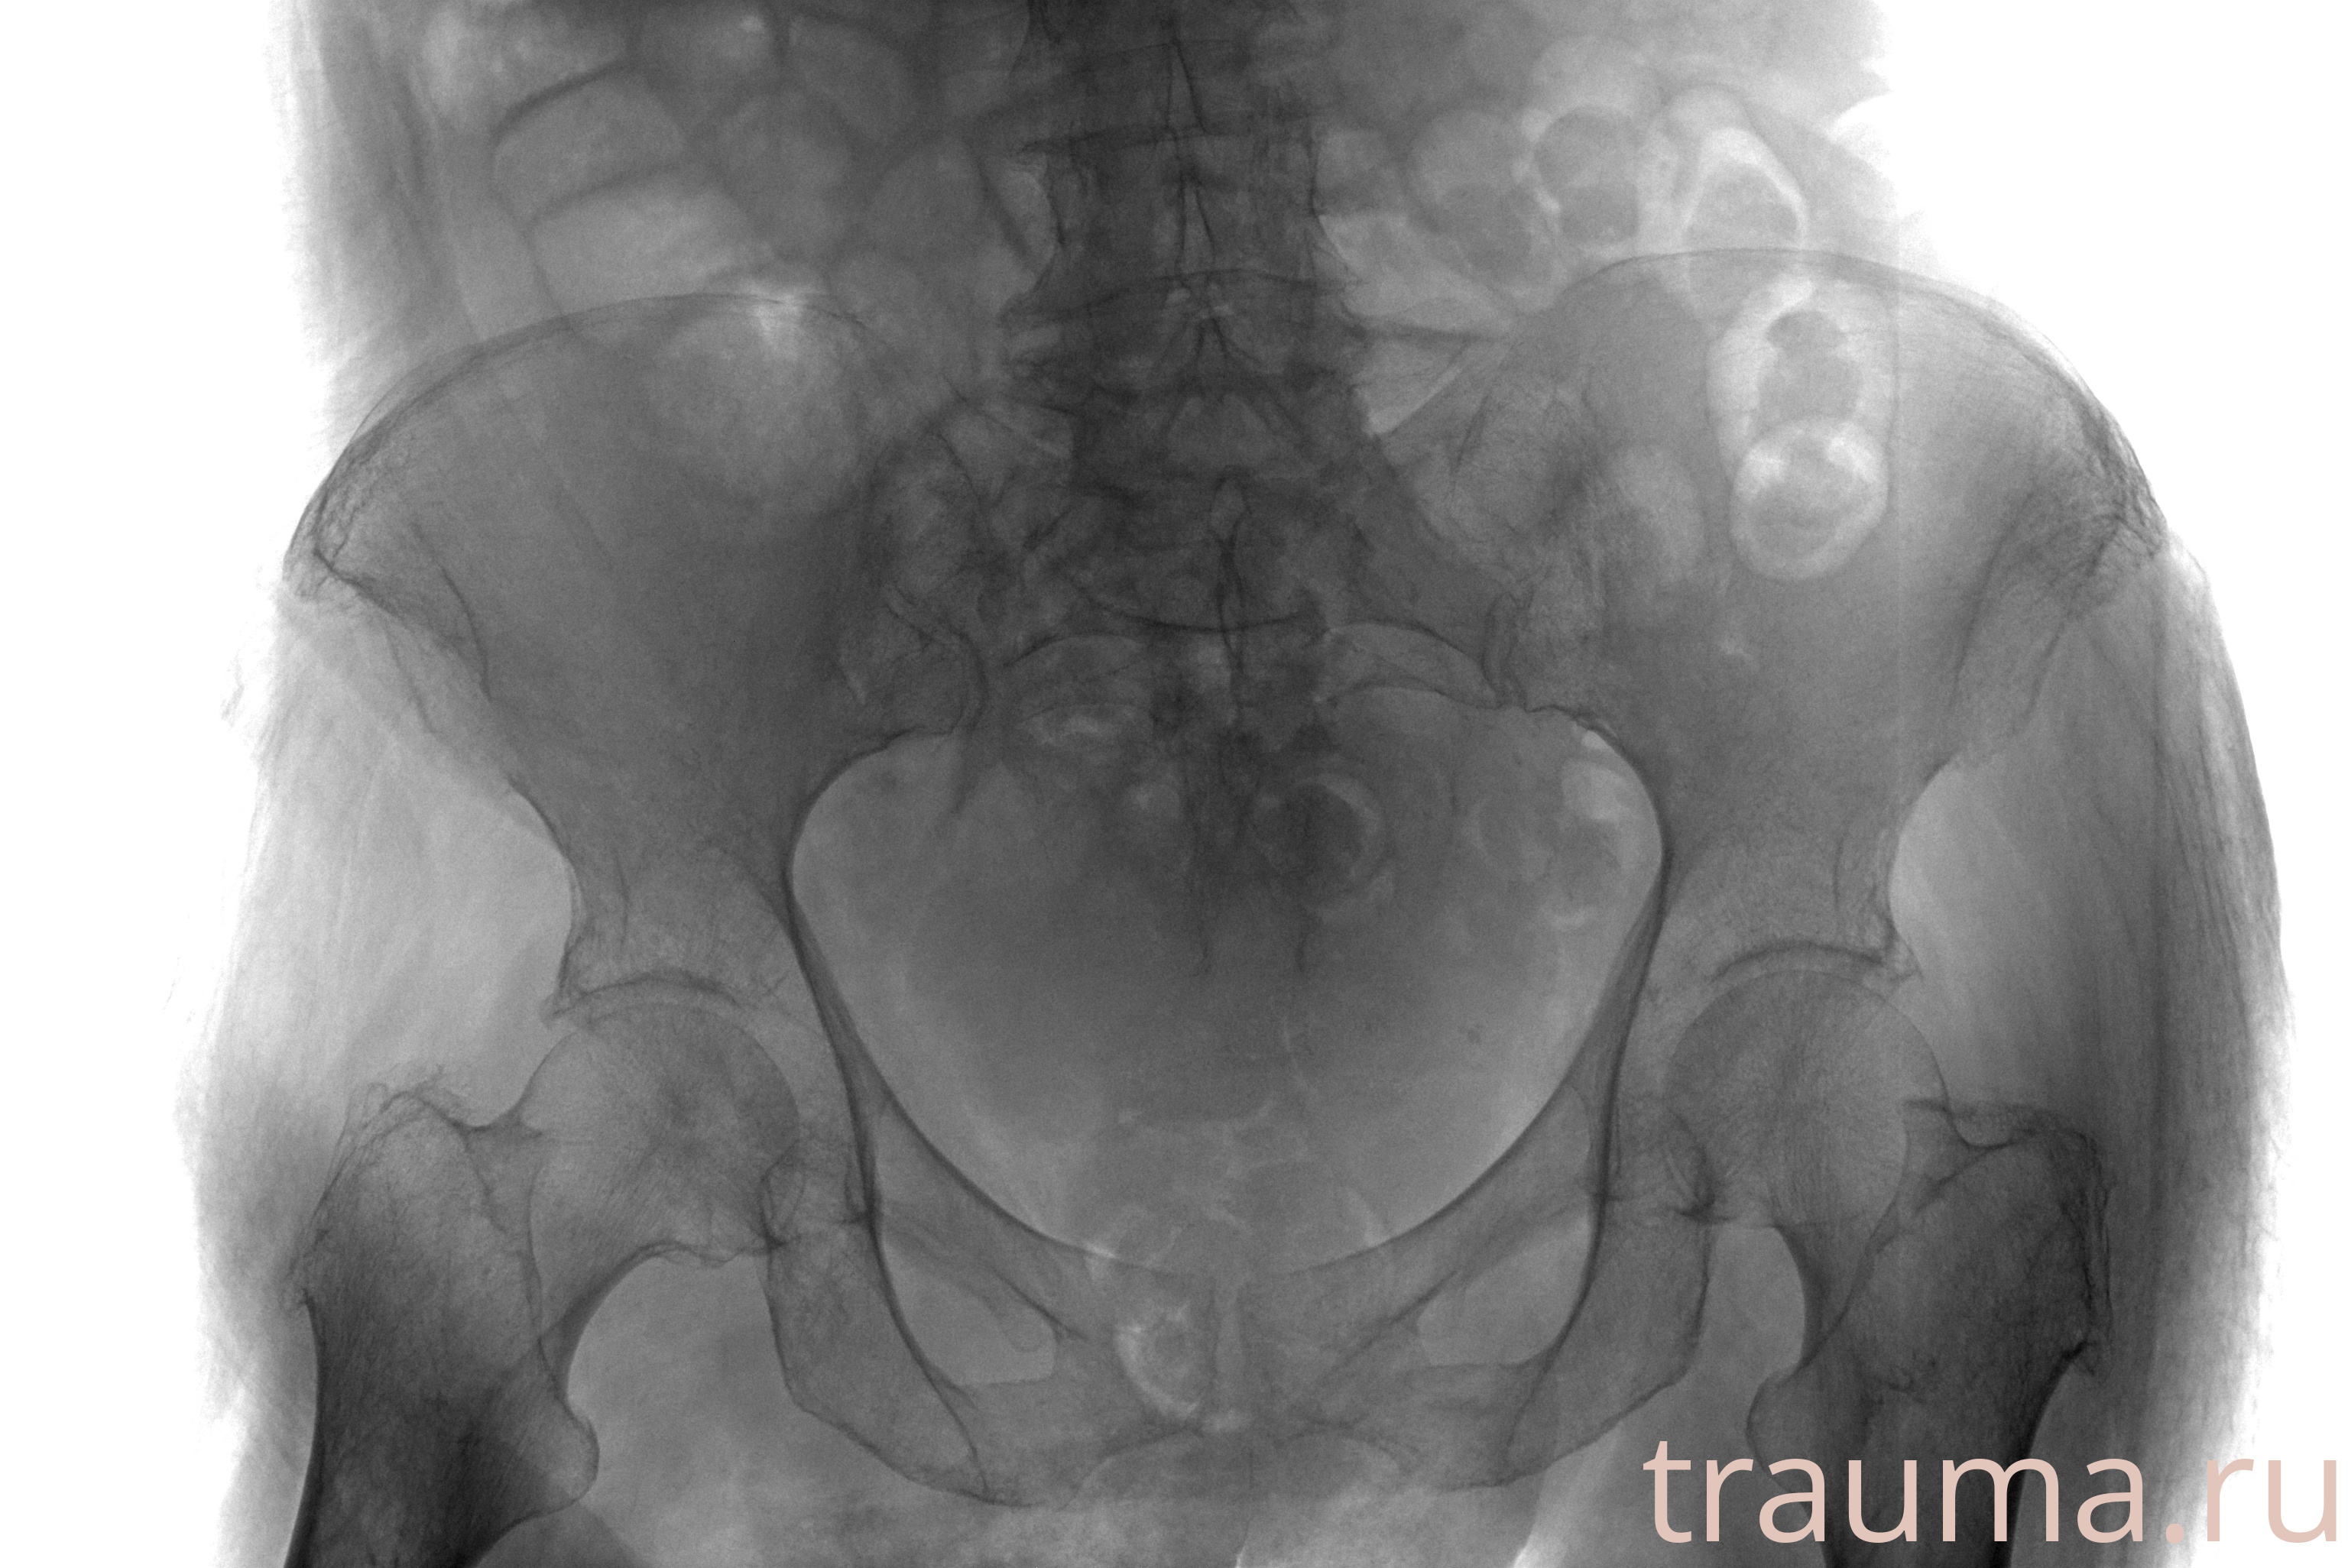

Рентген на дому: по вашему адресу приезжает врач-рентгенолог, травматолог-ортопед с мобильным рентгеновским аппаратом, проводит диагностику травмы или заболевания, делает необходимые рентгенограммы, дает рекомендации по дальнейшему лечению. Получить качественные снимки в домашних условиях возможно благодаря уникальной методике, разработанной МосРентген Центром для института  Склифосовского